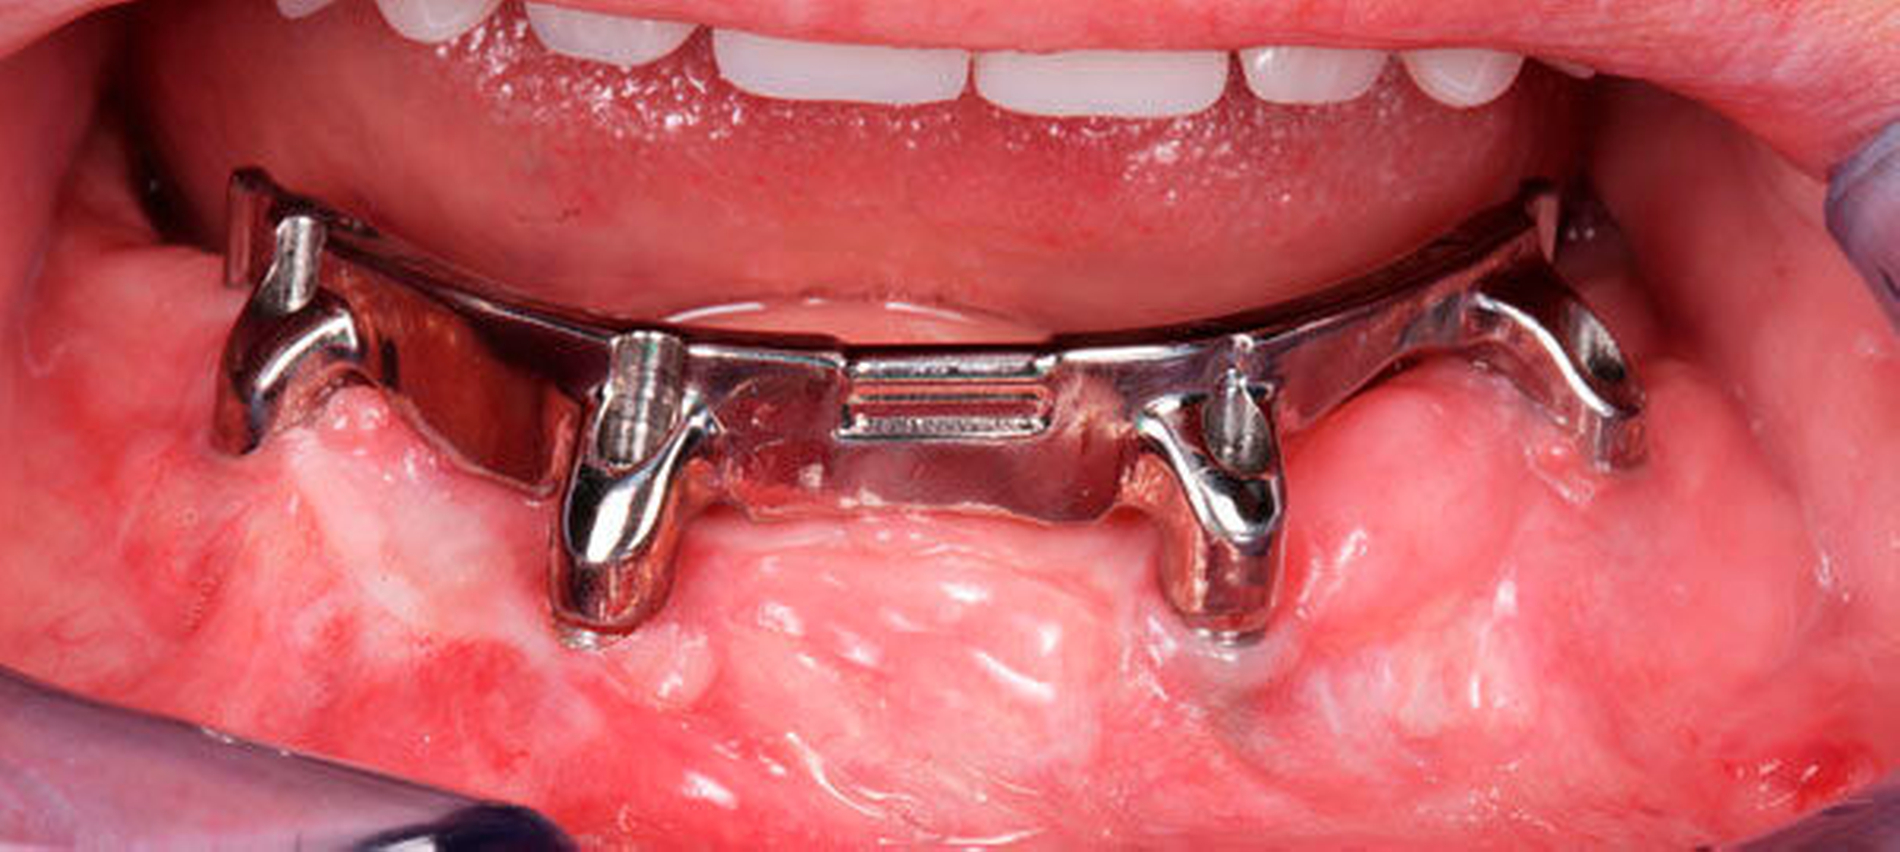

Die chirurgische Platzierung von Zahnimplantaten, das heißt die eigentliche Implantation, und die nachfolgende prothetische Versorgung dieser Implantate liegen nicht immer in einer Hand, sondern werden zum Teil von zwei verschiedenen Behandlern durchgeführt. Eine solche Arbeitsteilung hat durchaus Vorzüge: Aus der Allgemeinchirurgie wissen wir, dass Operateure mit großer Behandlungsroutine (hohe Fallzahlen pro Jahr) signifikant bessere Ergebnisse erzielen [Halm et al., 2002]. Doch geteilte Zuständigkeiten bergen auch Fallstricke: Wenn die Implantation und die nachfolgende prothetische Versorgung nicht gemeinsam geplant oder zumindest aufeinander abgestimmt werden, stellen sich im Fall eines ungünstigen Endresultats (Behandlungsfehler-Vorwurf) Fragen der Verantwortlichkeit. Man denke etwa an einen Fall, in dem ein Fachchirurg Implantate setzt, die aus Sicht des Implantatprothetikers falsch positioniert sind (Abbildungen 1, 2, 4, 5 und 6).

Letzterem bleibt nur die Wahl zwischen der Ablehnung der Weiterbehandlung und der Empfehlung einer aufwendigen und substanzverlustträchtigen Revision der Implantate (beides mutet dem betroffenen Patienten einiges zu) oder einer „Kompromissbehandlung“ mit dem Ziel, die invasive Revision der gesetzten Implantate abzuwenden und so den Schaden für den Patienten zu begrenzen. Heikel wird es insbesondere dann, wenn der Prothetiker in bester Absicht eine solche Kompromissbehandlung wagt, diese sich aber als nicht alltagstauglich erweist und der Patient schlussendlich Klage erhebt.

Hier kann es unter Umständen schwerfallen, die Verantwortung zuzuweisen: Liegt die Schuld beim Chirurgen, der die Implantate an ungünstiger Stelle gesetzt hat, oder beim Prothetiker, der sich nolens volens auf diese Situation eingelassen und ein letztlich unzureichendes Behandlungsergebnis erzielt hat? Aus fachlicher und ethischer Sicht ist die eigentliche Ursache für das insuffiziente Behandlungsergebnis beim Chirurgen zu suchen. Juristisch gesehen trägt dagegen jedoch der Implantatprothetiker die unmittelbare Verantwortung für das Behandlungsergebnis, da er die insuffiziente Suprakonstruktion geplant und eingegliedert hat. Rechtlich verhängnisvoll wird dieses Vorgehen insbesondere dann, wenn er den Patienten nicht explizit über den Kompromiss- und Versuchscharakter seiner Versorgung aufgeklärt hat oder das Aufklärungsgespräch und das Einverständnis des Patienten zur eigenen juristischen Absicherung nicht sorgsam dokumentiert hat.